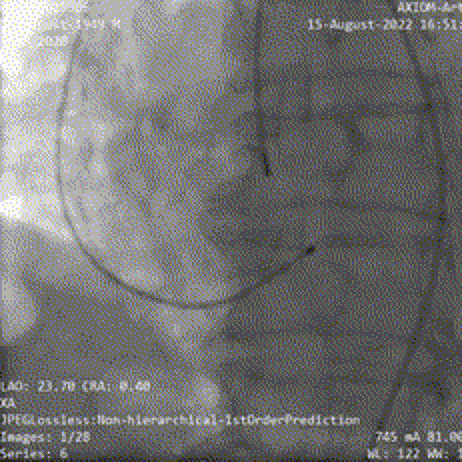

瓣膜释放到工作位后造影显示瓣膜流入端压缩较明显,瓣膜位置良好,冠脉显影正常,脱钩后瓣膜形态、位置良好,少量瓣周漏,弓部造影未见明显异常;

工作位造影

瓣膜释放脱钩

最终造影

弓部造影